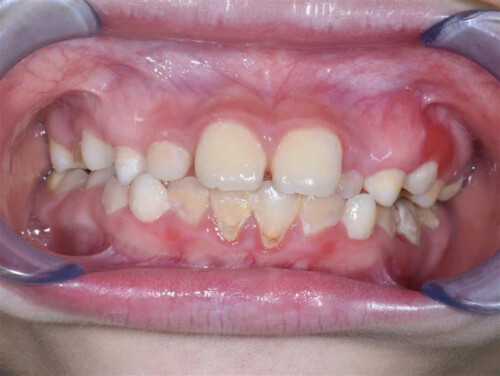

II.TRIỆU CHỨNG BỆNH VIÊM LỢI

Bệnh viêm lợi thường ít khi đau vì vậy người bệnh có thể bị viêm mà không biết. Các dấu hiệu và triệu chứng viêm lợi có thể có là:

- Lợi sưng nề

- Lợi teo rút

- Lợi chảy máu một cách dễ dàng khi dùng bàn chải đánh răng hoặc chỉ nha khoa, có thể nhận biết qua màu đỏ hoặc hồng trên bàn chải hay chỉ nha khoa

- Sự thay đổi màu sắc lợi răng từ một màu hồng khỏe mạnh đến nâu sẫm đỏ

- Có thể thường xuyên bị loét miệng

- Hơi thở có mùi hôi

- Có cảm giác đau khi nha

Chẩn đoán viêm lợi cần dựa vào triệu chứng viêm lợi như: lợi sưng đỏ, có mảng bám và dễ chảy máu. Bên cạnh đó cần kiểm tra cả răng, lợi răng và lưỡi một cách tổng quát, tìm các mảng bám và cao răng tích tụ để chẩn đoán nguyên nhân